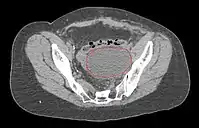

- CT of abdomen/pelvis typically not necessary, unless suspicion of extra-pelvic disease

- MRI is best modality for assessing myometrial invasion and cervical involvement, but provides no additional information if surgery is planned anyway

- Symptomatic lymphoceles are typically managed initially with percutaneous CT-guided drainage, surgical therapy may be required

- Postoperative Lymphocele